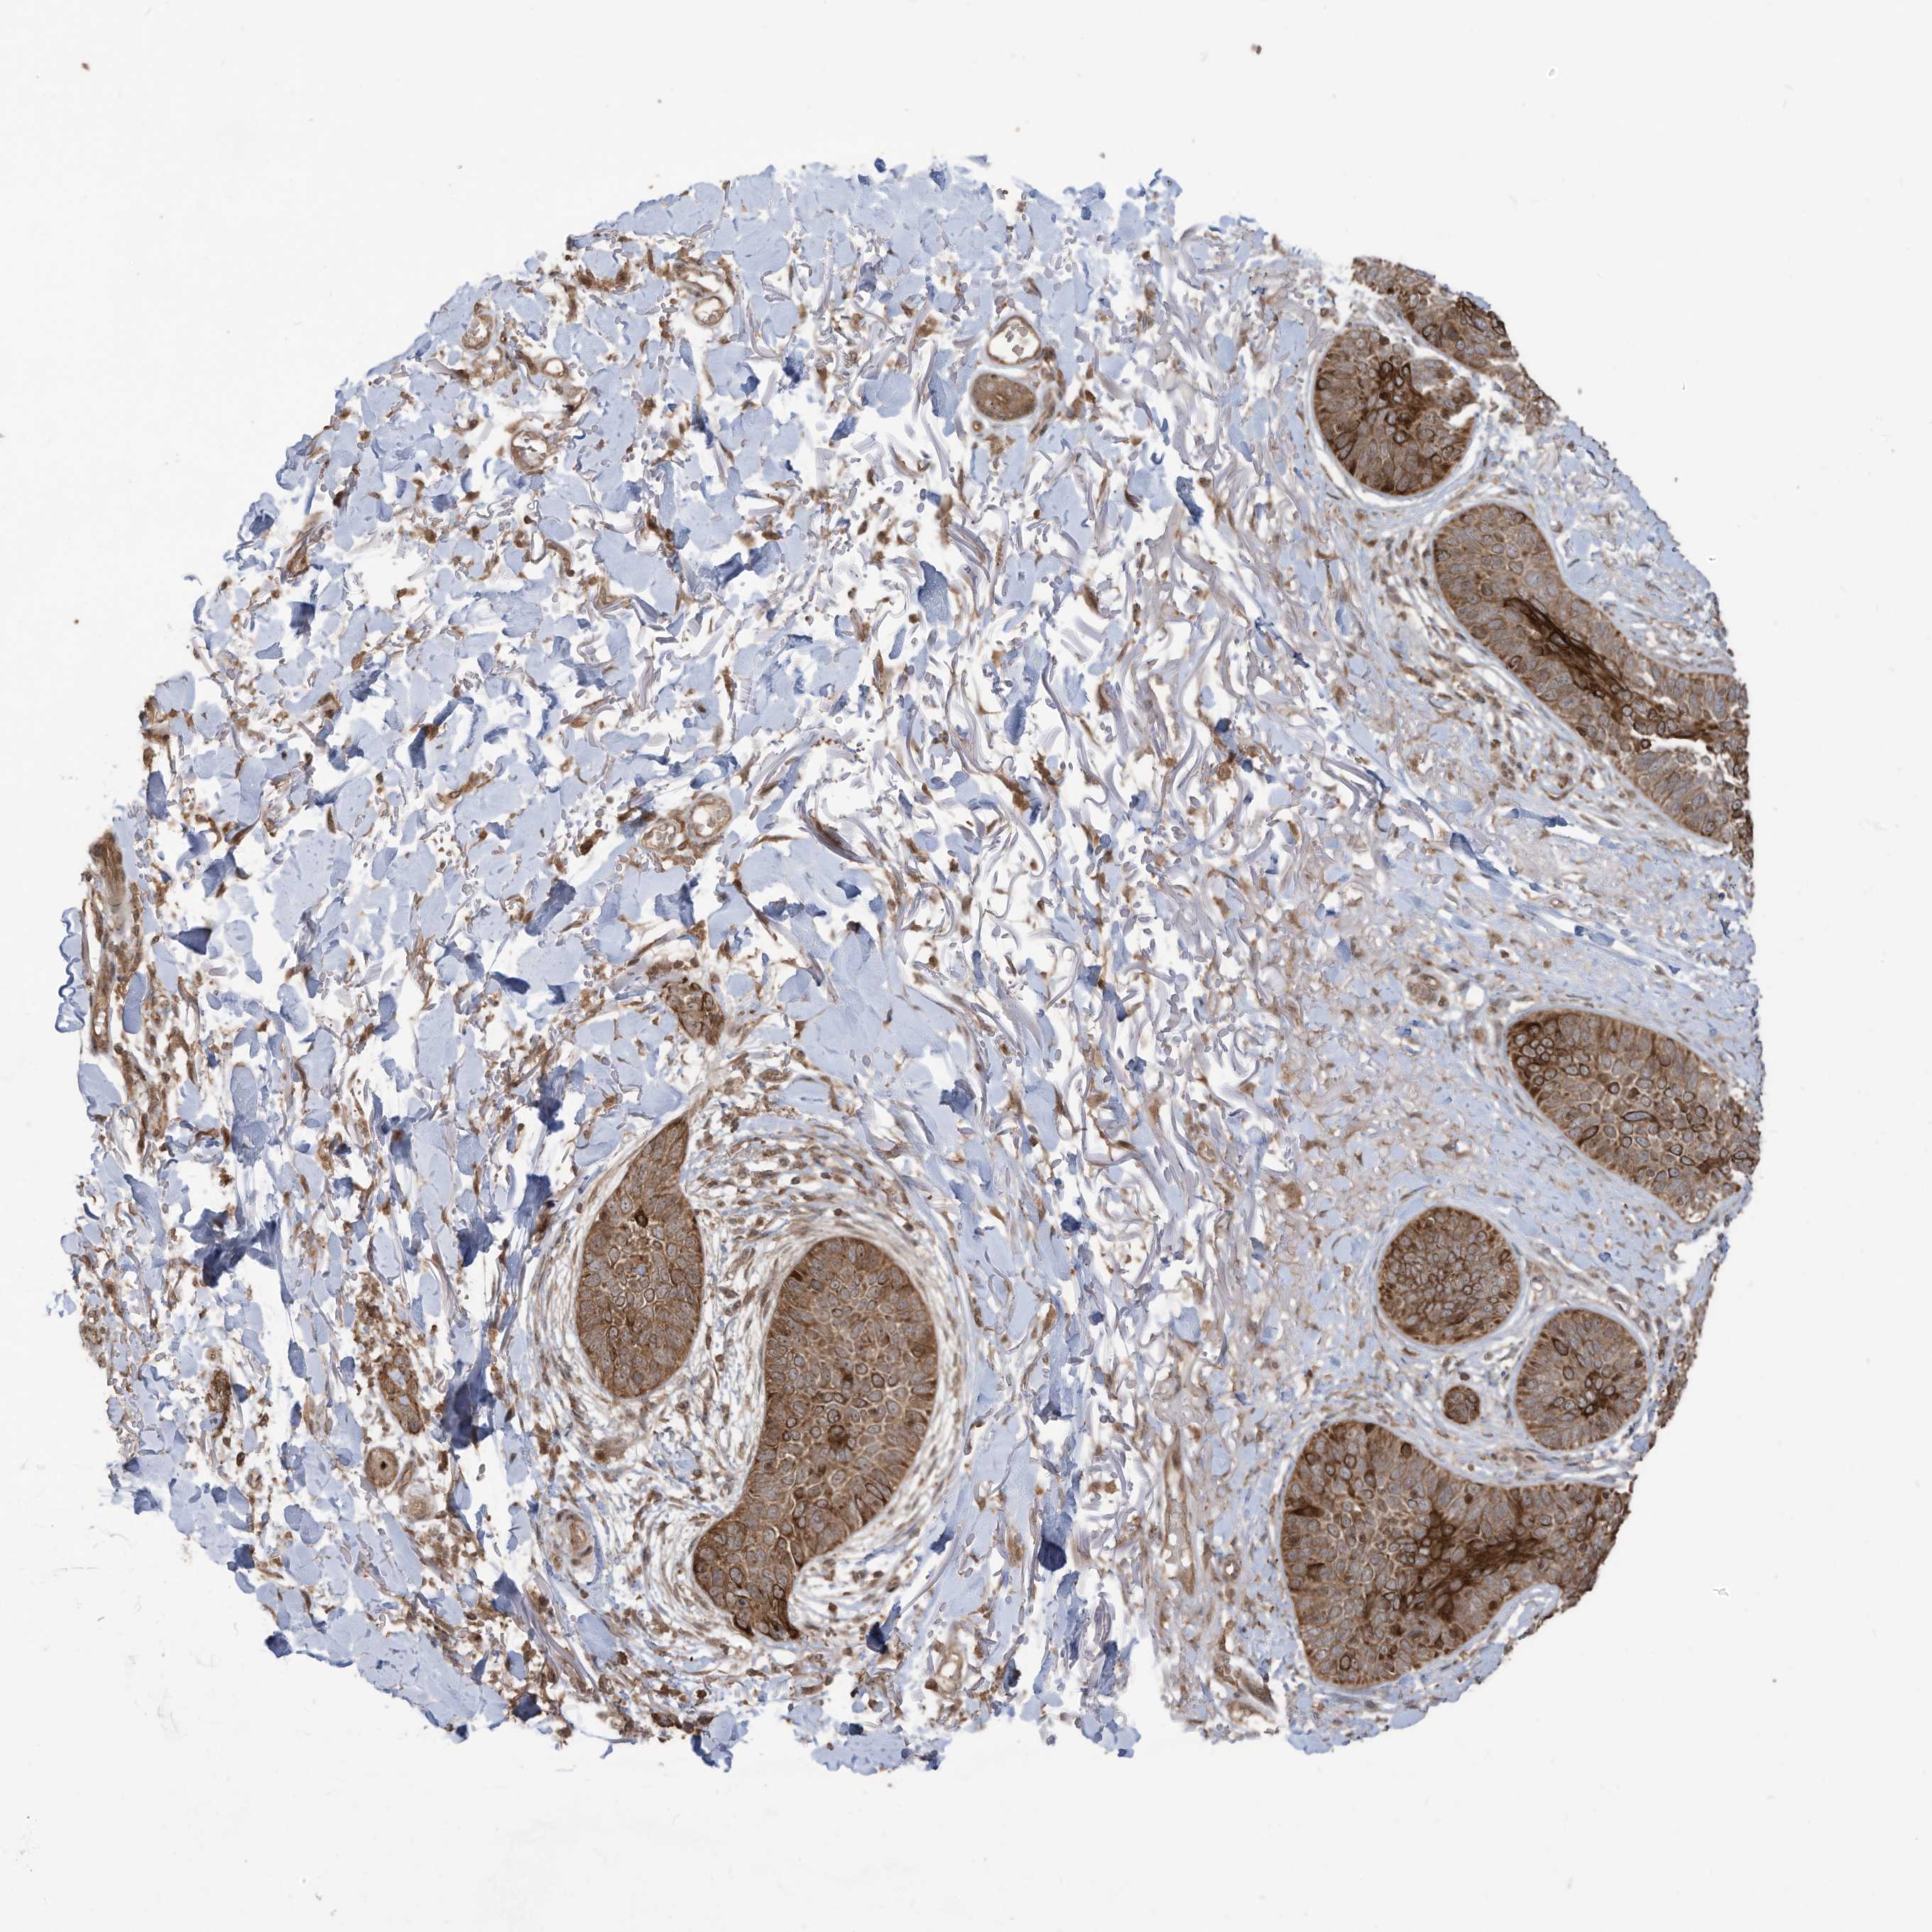

SKIN CANCER - Protein expressioni

A mouse-over function shows sample information and annotation data. Click on an image to view it in a full screen mode. Samples can be filtered based on level of antibody staining by selecting one or several of the following categories: high, medium, low and not detected. The assay and annotation is described here.

Each image is clickable and will lead to virtual microscopy that enables deeper exploration of all samples and also displays staining intensity scores, fraction scores and subcellular localization as well as patient and tissue information for each sample.

Antibody HPA034557

Staining

Medium

Intensity

Weak

Quantity

<25%

Location

Cytoplasmic/membranous

Squamous cell carcinoma, NOS